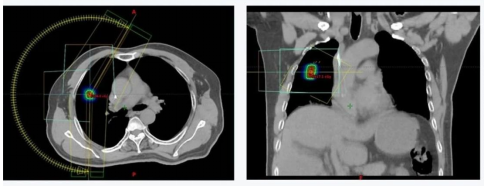

是一种先进的放射治疗技术,利用CT、MRI、PET-CT等先进影像技术,精确确定肿瘤的位置、大小和形状,误差通常控制在毫米级别,确保放射线束精准聚焦于肿瘤靶区,在短时间内给予肿瘤高剂量辐射,单次照射剂量较大(通常5-12Gy/次),分次少(一般2-10次),快速摧毁肿瘤细胞,效果类似手术切除。由于高精度和高剂量特性,能有效减少对周围正常组织的损伤,降低副作用(如恶心、疲劳、皮肤反应等),患者耐受性较好。

是一种先进的放射治疗技术,结合了适形放疗和调强放疗的优势,通过多叶光栅(MLC)等技术,使射线照射野的形状与肿瘤的三维形状精确匹配,确保射线仅覆盖肿瘤区域,减少对周围正常组织的照射;在适形的基础上,进一步调整射线束的强度分布。通过计算机算法优化,根据不同部位肿瘤的敏感性和周围正常组织的位置,精确控制射线剂量,使肿瘤内部剂量分布更均匀,同时降低对邻近重要器官(如脊髓、脑干、视神经等)的照射剂量。

图像引导放射治疗(IGRT)结合放射治疗与实时影像监测,通过光学体表、超声、CBCT/CT、MRI等影像设备能够实时监测肿瘤的位置和形状变化,提高治疗的精确性。通过实时监测,IGRT能够及时发现并纠正治疗过程中的偏差,降低正常组织的损伤风险。适用于肿瘤位置不固定或形状易变的病例,如肺癌、肝癌等。此外,在复发性肿瘤和需要高精度治疗的病例中也显示出良好的效果。